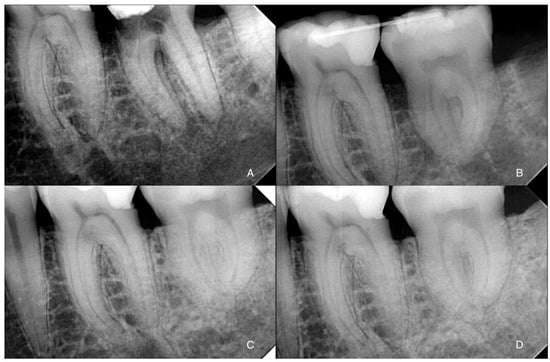

Tooth 3.7 had a very different root conformation compared to tooth 3.8. Given the hardness of the mandibular bone, we decided to prepare a surgical guide for the preparation of the recipient site with implant drills. Using a specific software for guided implantology (RealGUIDE™ 5.0, 3DIEMME Srl, Como, Italy), the donor tooth (3.8) was segmented from the CBCT and virtually moved in the alveolar space of tooth 3.7. We designed the surgical guide mimicking the insertion of four implants superimposed on the roots of the donor tooth to prepare the recipient site appropriately (Figure 2A). Through bone-milling with the guides designed by the software, the obtained site would be able to receive the donor tooth.

Surgical planning resulted in two guides that were 3D-printed after exporting STL files. CARP models of both teeth were printed to evaluate the discrepancy between the milled recipient site and the teeth dimension (Figure 2B).

After this phase, the patient received a 6-week orthodontic pre-treatment to initiate teeth mobilization to simplify the extractions and activate the PDL. Four composite buttons (one buccal and one lingual in each tooth) were applied to the crowns of 3.7 and 3.8. Alternating forces were applied weekly, inserting a chain between the buccal buttons and then on the lingual ones. A separating rubber band was also inserted every week (Figure 2C).

Immediately before the procedure, the patient rinsed with Chlorhexidine 0.3% mouthwash for one minute, and the lips and perioral tissues were disinfected with a povidone-iodine solution. The anesthetic solution with 4% articaine with epinephrine (1:100,000) was delivered locally through an inferior alveolar nerve block and buccal infiltration. The surgery was performed flapless: tooth 3.7 was extracted through a magneto-dynamic device (Magnetic Mallet, Osseotouch, Varese, Italy). After 3.7 extraction and before 3.8 extraction, the recipient socket was prepared with the surgical guides using a specific guided-surgery implant drill kit (Anyridge, Megagen, Seoul, Republic of Korea). Subsequently, the CARP model of tooth 3.8 was inserted in the recipient socket to check the efficacy of the guided surgical protocol. Tooth 3.8 was extracted using forceps, taking care not to injure the PDL; the forces applied were slow and progressive to tear the collagen ligament fibers gently. The donor tooth was immediately inserted into the recipient site as soon as it was extracted, so the extra-alveolar time was approximately one second. No root surface modifications were performed on the donor tooth before the insertion in the socket. The transplanted tooth was then fixed with suspended sutures and a passive flexible wire bonded with a composite (Figure 1B and Figure 2D). An occlusal adjustment was necessary to reduce the occlusal forces.

Figure 2. (A) Planning of the template simulating the positioning of four dental implants superimposed to the donor tooth virtually moved in the recipient site (in green); (B) templates and CARP resin models of both the compromised and donor teeth; (C) pre-operative field showing the attachment for the initial orthodontic phase; (D) post-operative image with suspended sutures and wire fixing.